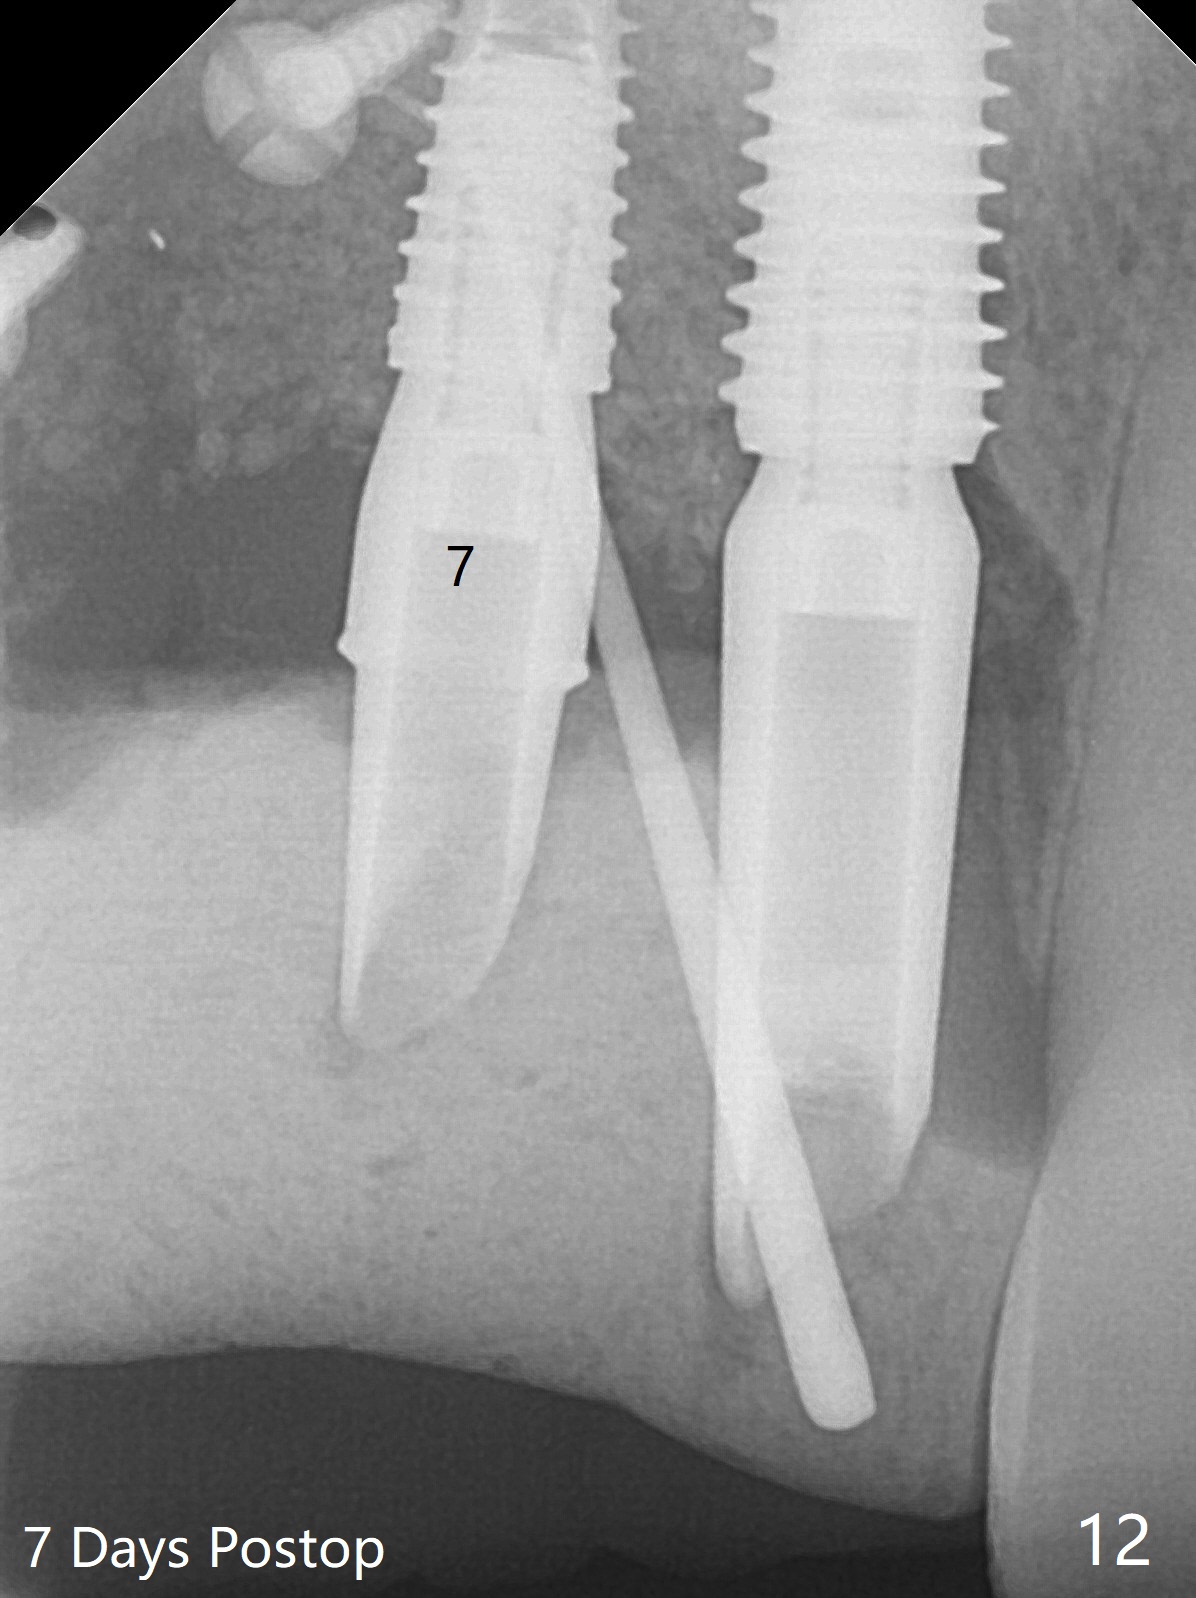

在6,7号牙位牙槽嵴切口,翻瓣,找不到上次放置的tenting screw,不过7号牙位骨质虽然低,够宽的,开始钻洞(图四),植入3.8乘8.5毫米植体,扭力足够(图五),近中舌侧暴露螺纹堆加骨粉(图五*),然后放置基台,再次在后者周围放置骨粉(图五至七),覆盖两张PRF膜后缝合(图八),最后在三个箭头周围放置牙周敷料。术后CT显示植体与tenting screws(图九,十箭头)有一定距离,但是5号牙植体颊侧根尖穿孔(图九 *)。如果植体不脱落,需做侧方切口植骨。术后七天7号植体腭侧肿胀(图十一 *),切开没有脓水,插入牙胶尖,它末端指向7号植体周围tenting screw。后者可能需要拔除,同时5号牙颊侧根尖植骨,但是为时太早,可能打搅骨粉生长。术后两周腭侧肿胀没有消失,但是不痛,继续观察。术后接近6个月,软组织正常(图十三),但是5,7植体周围没有骨质(图十四,五)。由于近中tenting screws周围软组织触痛(局麻不全情况下),螺钉取出(图十六,七(*)),而远中螺钉好像有帮助5植体螺纹骨粉撑起,所以留下(腭侧穿孔部分去除),最后放置粘性骨粉(图十八:*)和PRF膜(两张由7基台打孔固定)。